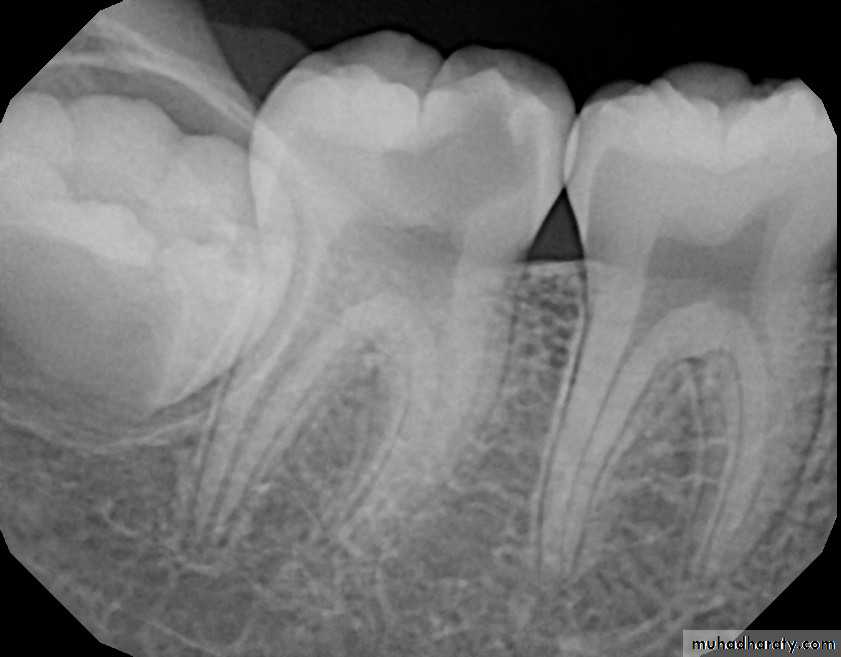

• CARIOUS LESIONS

• INVOLVING THE PULP

• DEEP CARIOUS LESION WITH PULPAL INVOLVEMENT